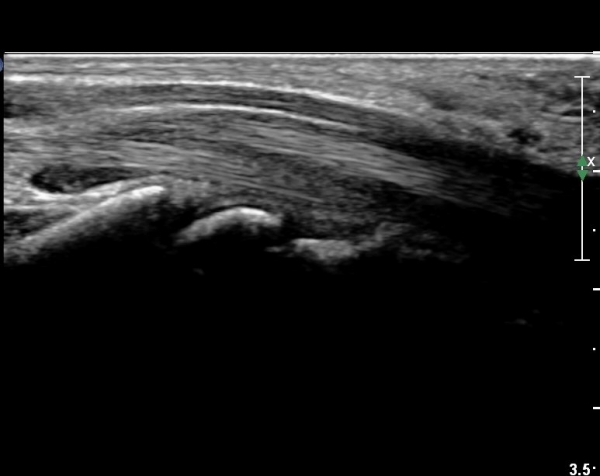

¼Õ¸ñ°ú ¼ö±Ù°ü±ÙÀ§ºÎ Ⱦ´Ü¸é°Ë»ç¿¡¼­  ÈûÁÙÀÇ ºñÈÄ¿Í ÈûÁÙ ÁÖÀ§ Ȱ¾×¸· ºñÈİ¡ °üÂûµÇ³ª

Á¤Áß½Å°æ ºÎÁ¾Àº °üÂûµÇÁö ¾Ê´Â´Ù(»çÁø 3, 4).